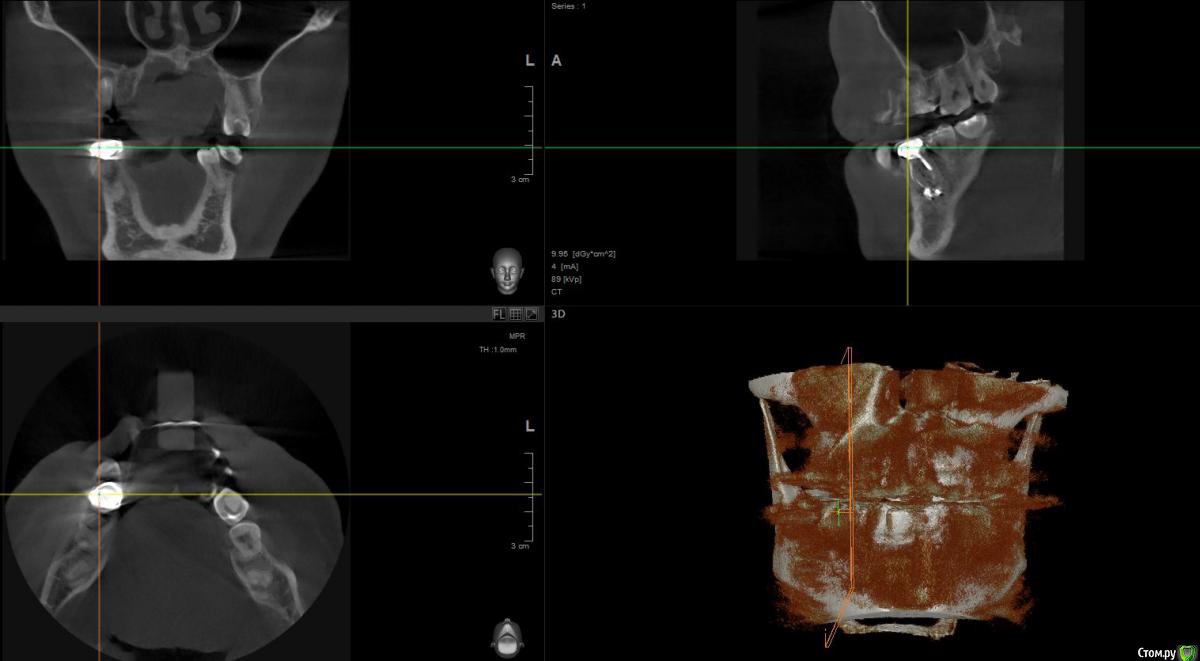

1 год назад были установлены 3 коронки. см Фото. После появления свища над верхней коронкой обратился к стоматологам.На фото 2 верхние коронки уже спилены и начато повторно лечение одного зуба,за мой счет конечно.

По результатам снимков след.вывод. Две верхние коронки снимать и лечить каналы , так там воспаление. Под нижней коронкой небольшое воспаление,но сказали пока его не трогать ,но взять под наблюдение.

post-48565-0-53110900-1469537787_thumb.jpg